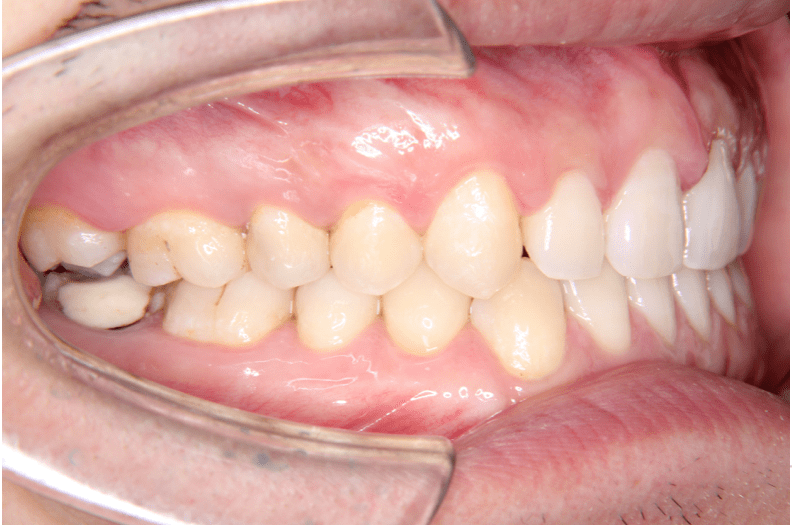

治療後(左)

上下開いていた症例ですので、下を閉じてから上を閉じる計画を立てました。

症例情報:

【患者】 20代男性

【主訴】 前歯のすき間がきになる。

【診断】 空隙歯列

【抜歯の有無】 非抜歯

【治療期間】2年0ヶ月 通院回数15回

【治療内容】親知らずを抜歯した後、マウスピース型カスタムメイド矯正歯科装置(製品名インビザライン 完成物薬機法対象外)を使用して主訴である叢生の改善を行いました。

【費用】88万(税込)